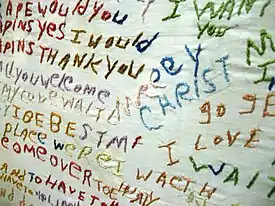

Una paciente esquizofrénica bordó por sí misma esta tela, lo que nos da cierta idea sobre su desarreglo mental. Pieza que actualmente se expone en el Glore Psychiatric Museum. | ||